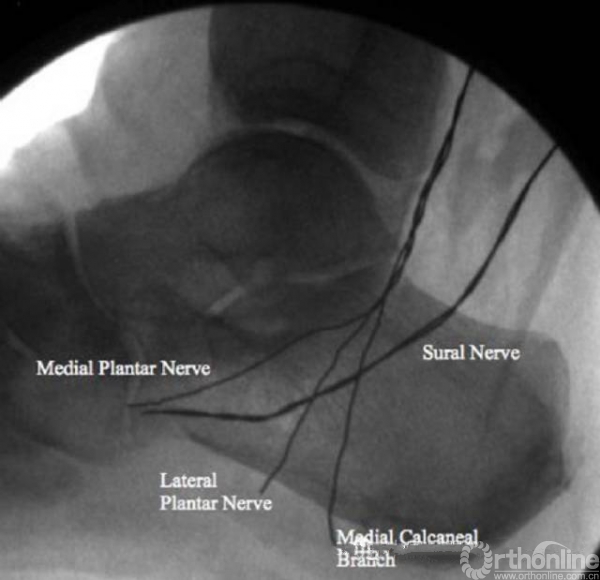

本研究选取了40只新鲜-冷冻的足标本,尸体平均年龄78.1岁,其中18男,22女。用可显影线绑定于腓肠神经、胫神经、足底内外侧神经上,然后行X线透视。观察各条神经和骨的关系。通过开放和经皮的跟骨截骨分别观察神经损伤以及神经和截骨平面的关系。

A线是标志线,显示自跟骨结节后上方向跖筋膜起点处走行

B线是A线的平行线,距最靠后的神经后方2mm,A线到B线之间的区域为安全区(图中阴影区)